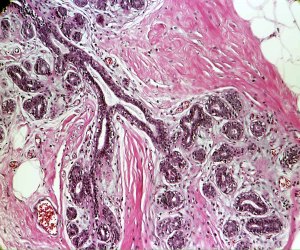

Day to Day at Pathology Visions

Every year we await the Pathology Visions conference, curious to see what the latest in digital pathology will be. This year’s conference was held in San Antonio, Texas, USA, and attended by numerous researchers and clinicians. Eric Glassy’s keynote, styled after “The Hitchhiker’s Guide to the Galaxy,” advocated for major areas in which digital pathology could be important in the future…..click here for more.

S99-1772-B2-10X1